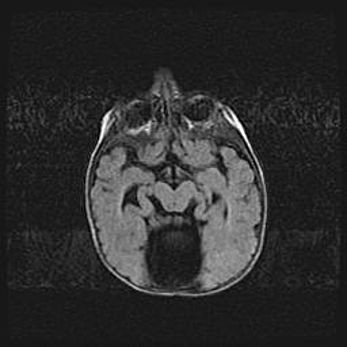

Неполная лизэнцефалия (пахигирия). Открытая гидроцефалия.

Возраст: 17 дней

Вес: 3110 г

Пол: мужской

Окружность головы: 33,5 см

Срок гестации: 35-36 недель

Лизэнцефалия—недоразвитие корковой пластинки и мозговых извилин в результате нарушения миграции нейронов коры. Поверхность мозговых полушарий гладкая. Микроскопически выявляется отсутствие нормальных слоев коры и скопление групп нейронов в подкорковом белом веществе.

Пахигирия—уменьшение числа вторичных извилин. В пораженном полушарии нервные клетки образуют толстый недифференцированный слой с неправильно расположенными нервными волокнами и группами гетеротопных клеток. Нервные клетки незрелые. Белое вещество истончено. При этом нередко аномально развит корково-спинномозговой путь.